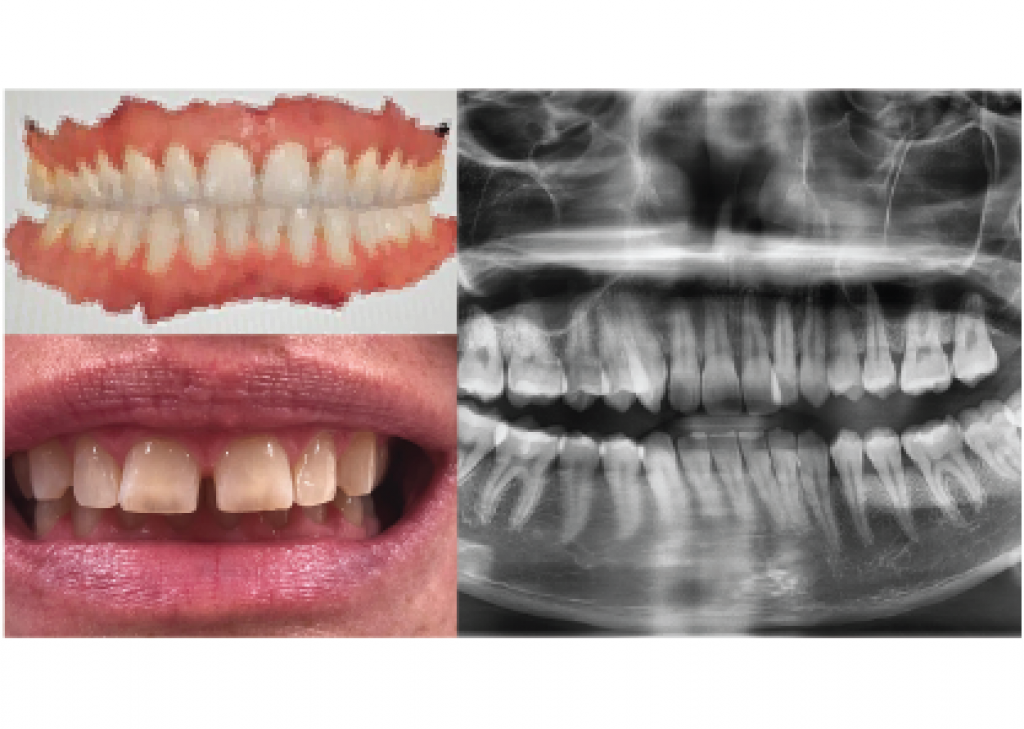

What we need to create a 3D-Plan:

- OPG (Panoramic X-ray)

- Clinical photos (e.g. with smartphone)

- Intraoral scans